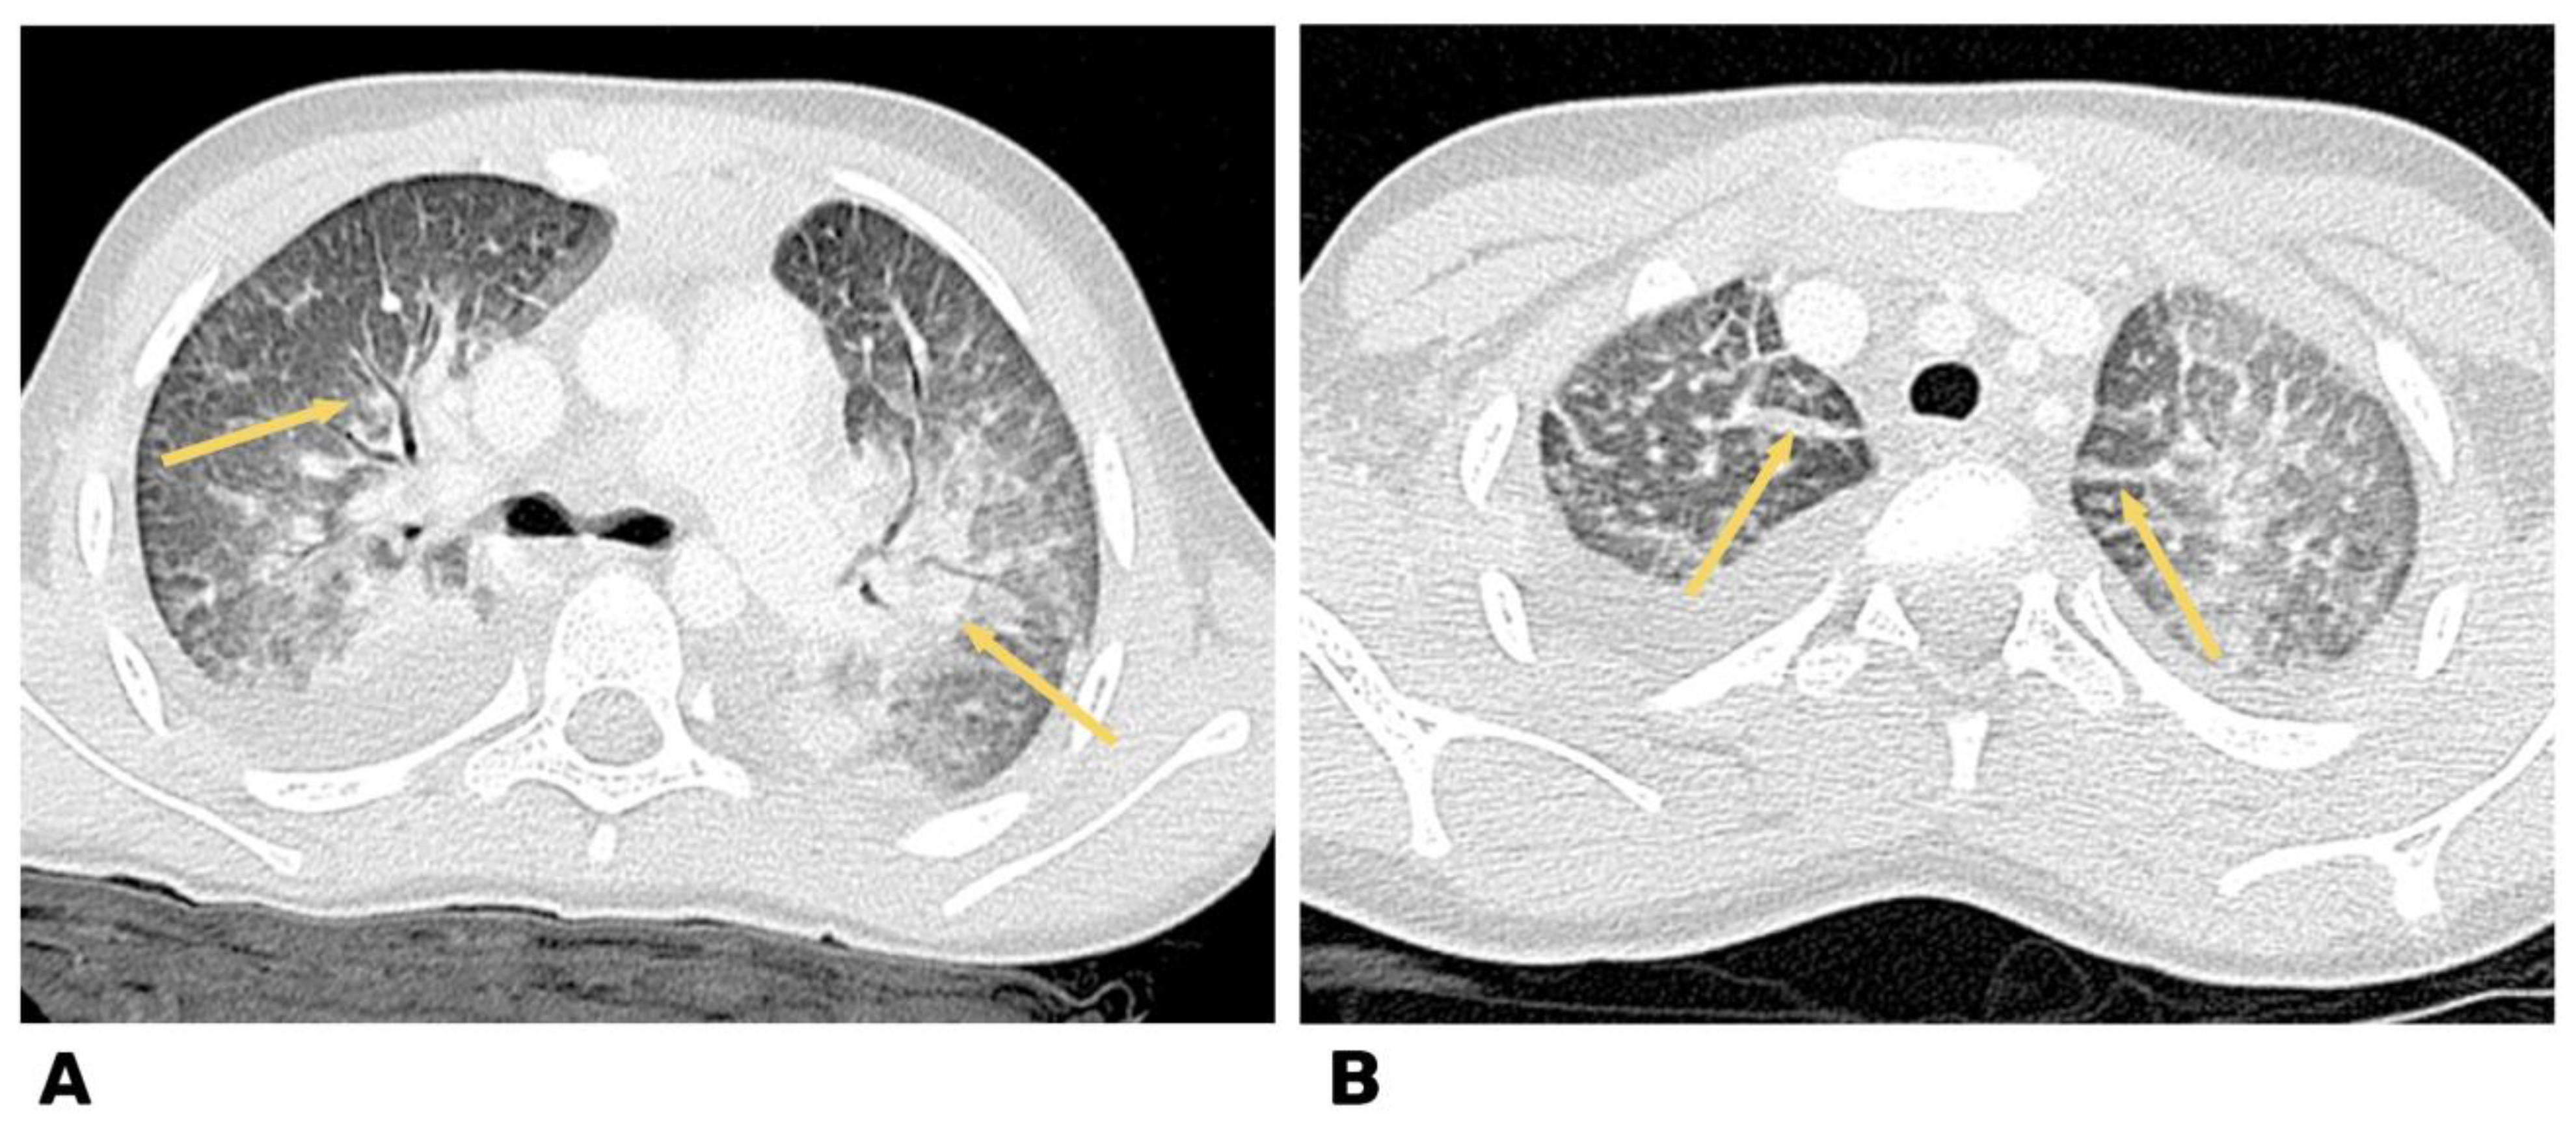

The CT and CT-angiography, a diffuse decrease of the lung pneumatization was diagnosed due to extensive confluent “ground-glass” attenuation, and free fluid up to 25 and 30 mm was determined in the pleural cavities on the right and left, respectively. The signs of left-sided thromboembolism of subsegmental branches of the A8 pulmonary artery and heterogeneity of pneumatization were diagnosed (Figure 4).

Signs of the signal enhancement on Tirm due to edema of the IVS myocardium were revealed on the heart MRI data with contrast, which indicated inflammatory changes in the myocardium three weeks later (Figure 5 and Figure 6).

Heart CT, axial and coronal angiography, and pulmonary mode after 4 weeks.

From the ECG, there was also a positive trend in the form of improved repolarization processes.

From the brain MRI, there was restoration of patency of the right MCA with an MR picture of postischemic cystic−gliotic changes in the territory of the right middle cerebral artery observed (Figure 7).

Figure 7.

Brain MRI. Arrows indicate postischemic cystic−glial changes in the territory of the right middle cerebral artery.

We diagnosed long-COVID-19, taking into account the age of the patient; epidemiological data (contact with parents with COVID-19 and positive IgM and IgG to SARS-CoV-2); viral pneumonia; and the development of severe multisystem organ pathology with involvement of the gastrointestinal tract (abdominal syndrome), heart (with the development of acute myocarditis), and CNS (ischemic stroke in the territory of the right MCA) that appeared after the onset of the disease.

During the period of hospitalization, there was a clear positive trend in the patient: normalization of the level of troponin I and a decrease in NT-proBNP, normalization of the myocardial contractility left ventricular, and improvement of the regional contractility. There was an improvement in muscle strength in the extremities and an increase in motion, positive dynamics of the neurological status, and thrombus lysis in the MCA, as confirmed by brain MRI.